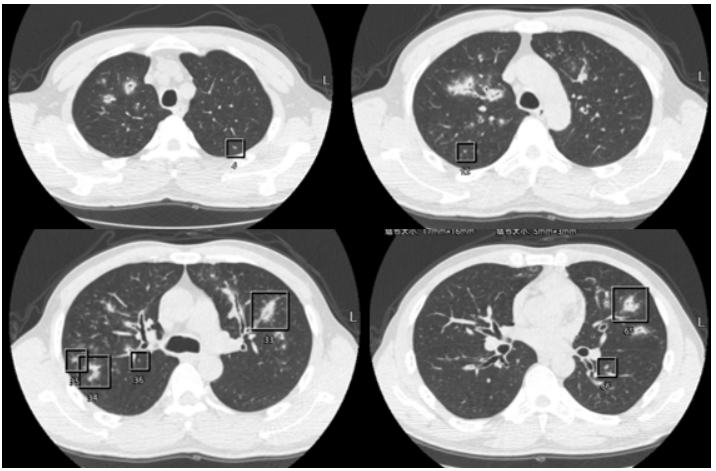

1月30日开始发热,热峰39℃,伴夜间呛咳。2月1日痰中带血,脓血痰,偶伴小量咯血(10 ml左右)。2月2日胸部CT可见空洞病灶进展(图4)

图4  复查胸部CT(2023-02-02)

患者热峰下降, 但体温仍有波动。2月9日复查胸部CT见右上肺病灶吸收, 左上肺进展(图5)。患者仍间断发热, 热峰38℃, 伴脓血性痰液。

图5  复查胸部CT(2023-02-09)